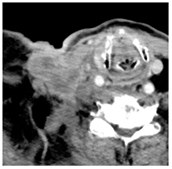

| 1 | 75–100 | 860 | ![]() Axial post-contrast fat-suppressed T1-weighted MRI shows a solidly enhancing left retroarticular tumor. | ![]() Axial CT image obtained 1 day after injection shows the NBTXR3 nanoparticles (arrows) in the tumor with leakage into the surrounding soft tissues. |